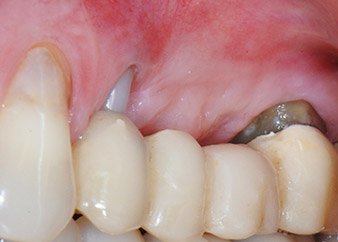

apical periodontal lesion at tooth 24

Fig. 1: 58-year-old patient. Preoperative radiograph showing an apical periodontal lesion at tooth 24 and horizontal loss of alveolar bone in the second quadrant.

A 58-year-old female patient complained of pain and increased mobility of her bridge abutment tooth 24. Periodontal inflammation was present with pocket depths of 7 mm mesiobuccally and more than 12 mm distally, as well as third-degree furcation involvement. Moreover, the radiograph revealed an extensive periodontal lesion around the apical region of the (alio loco) endodontically pretreated tooth 24 (Fig. 1).

One year earlier, teeth 25 and 26 had been extracted due to trauma and for endo-perio reasons, prior to the placement of the bridge. A combined endo-perio lesion was diagnosed for tooth 24, of unclear aetiology. The patient wanted to keep her bridge abutment teeth 24 and 27 and would not accept a final, or even temporary, removable prosthesis. Therefore, it was agreed to make all efforts to retain both teeth, in spite of their poor prognosis as based on radiological and clinical findings.